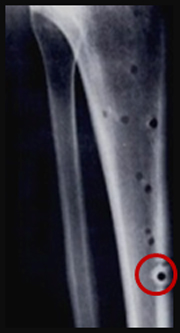

An experimental study was performed to investigate the effects of spindle speed, feed rate, and depth of drilling on the temperature distribution during drilling of the cortical section of the bovine femur. In an effort to reduce measurement uncertainties, a new approach for temperature measurements during bone drilling is presented in this study. The new approach is based on a setup for precise positioning of multiple thermocouples, automated data logging system, and a computer numerically controlled machining system (CNC). A battery of experiments has been performed to assess the uncertainty and repeatability of the new approach, which display adequate results. Subsequently, a parametric study was conducted to determine the effects of spindle speed, feed rate, hole depth, and thermocouple location on the measured bone temperature. This study suggests that the exposure time during bone drilling far exceeds the commonly accepted threshold for thermal injury, which may prevail at significant distances from the drilled hole. Results of this study suggest that the correlation of the thermal exposure threshold for bone injury and viability should be further explored.